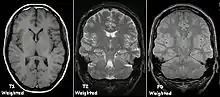

Each tissue returns to its equilibrium state after excitation by the independent relaxation processes of T1 (spin-lattice; that is, magnetization in the same direction as the static magnetic field) and T2 (spin-spin; transverse to the static magnetic field). To create a T1-weighted image, magnetization is allowed to recover before measuring the MR signal by changing the repetition time (TR). This image weighting is useful for assessing the cerebral cortex, identifying fatty tissue, characterizing focal liver lesions, and in general, obtaining morphological information, as well as for post-contrast imaging. To create a T2-weighted image, magnetization is allowed to decay before measuring the MR signal by changing the echo time (TE). This image weighting is useful for detecting edema and inflammation, revealing white matter lesions, and assessing zonal anatomy in the prostate and uterus.

The standard display of MR images is to represent fluid characteristics in black-and-white images, where different tissues turn out as follows:

| Signal | T1-weighted | T2-weighted |

|---|---|---|

| High |

|

| Intermediate | Gray matter darker than white matter[23] | White matter darker than grey matter[23] |

| Low |